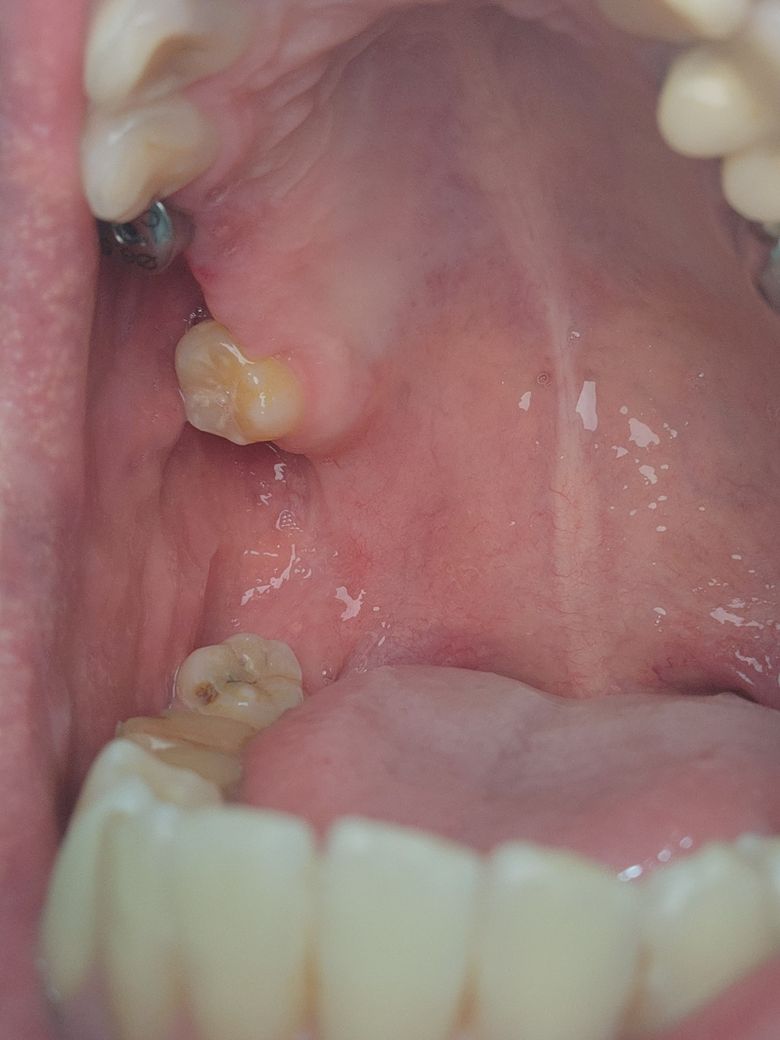

구내염 일까요~? 임플란트 염증 일까요~?

8월7일 이번주 월요일부터 잇몸 부위가 따가웠는데

양치질을 쎄게했나 싶어 지켜보았습니다.

금요일이 될때까지 따가운데

의사선생님이 보시기에는

구내염 일까요~? 임플란트 염증 일까요?

현재 사진상으로는 임플란트 염증일 가능성도 있기에 통증이 지속되는 경우 치과를 방문하여 진료를 받길 권합니다.

구내염이나 임플란트 염증은 아닌거 같습니다. 그냥 잇몸에 상처가 좀 난거 같으니 너무 걱정하지 않으셔도 될것같습니다.

잇몸에 상처가 있는듯 보입니다.

해당부위로 음식이 자극되거나 하지는 않았는지 확인해보는것이 좋습니다.

손상된 잇몸은 보통 2주정도 지나면 회복됩니다.

그이후에도 염증이 줄어들지 않는다면 치과에서 진료를 받는것이 좋습니다 .

임플란트 염증이면 붓고 피가나는 등의 증상이 나타납니다. 사진상으론 구내염으로 보입니다.